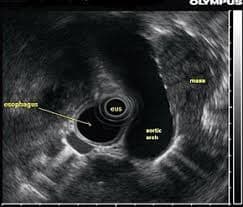

內窺鏡超聲波(EUS)結合了內窺鏡檢查與超聲波技術,能夠創建消化道及其附近器官的詳細影像。這本指南將解釋EUS可以揭示的內容、為何使用它及如何理解其發現。

EUS是一種微創程序,小型超聲探頭連接在內窺鏡的末端。它允許醫生獲取消化道、淋巴結及周圍結構的高解析度圖像。讓我們來探索這種先進影像技術的具體細節。

- 詳細的消化道影像: 可視化食道、胃及十二指腸的層次。

- 胰臟和膽道評估: 清晰看到胰臟、膽囊、膽管及周圍結構。

- 淋巴結影像: 詳細評估位於消化道附近的淋巴結,以檢查癌症擴散或炎症。

- 腫瘤分期: 精確分期消化系統內的腫瘤,有助於治療規劃。